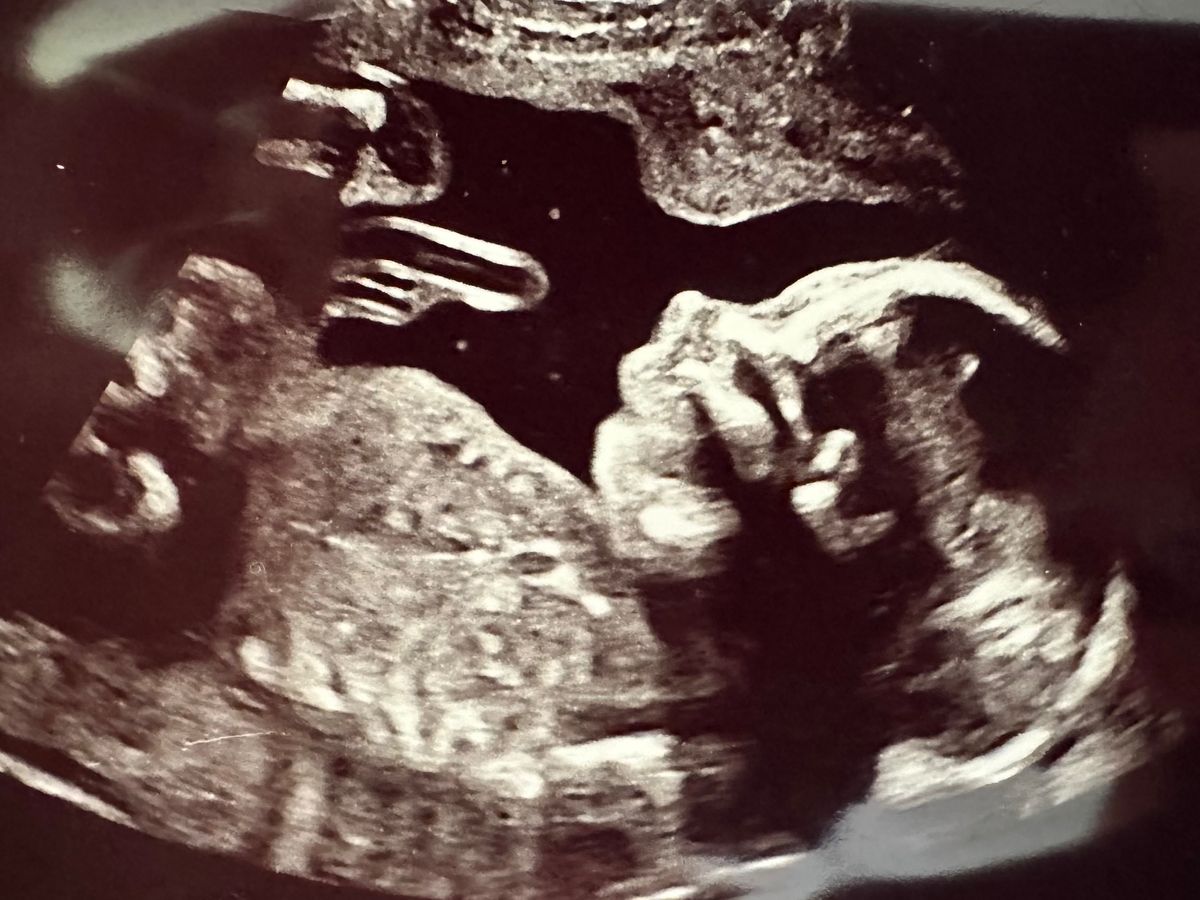

Last week we had a scan that told us our baby's stomach was in her chest. We were given a referral to the fetal medicine team who later found that her stomach, liver and bowel were growing in the left side of her chest due to a congenital diaphragmatic hernia, pushing her heart into the right chest cavity. Leaving no room for her lungs to develop.

Despite there being surgeries to move her organs into place We were told her hernia was so severe that her lungs were not developed and she would be unable to take her first breath.